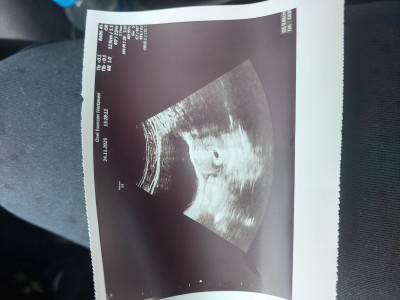

Kizlar 28 ekimde transfer oldum 8 kasimda sonucumu aldim.ve pozitif fakat şöyle bir karmaşıklık var kendi doktoruma göre 6+2 günlüğüm fakat baska bir doktora göre de 5 hafta içerisindeyim 17 kasimda kese gördük 24 kasimda kalp atışı duyarız dedi kendi doktorum kalp atışı yoktu ve yolk kesesi embriyo da yok dedi ve haftaya bakicaz ama iyi bisey degil dedi  ben baska doktora da gittim o doktor 5 hafta icinde olduğumu ve bu zamanlarda gozukmemesi normal dedi  bu dünkü kendi doktorumun yaptığı usg resmi büyük yuvarlak olan  diğeri de bu baska doktorun çektiği de bu